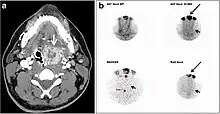

| CT scan and scintigraphy images of lingular ectopic thyroid | |

An ectopic thyroid, also called accessory thyroid gland, is a form of thyroid dysgenesis in which an entire or parts of the thyroid located in another part of the body than what is the usual case. A completely ectopic thyroid gland may be located anywhere along the path of the descent of the thyroid during its embryological development, although it is most commonly located at the base of the tongue, just posterior to the foramen cecum of the tongue. In this location, an aberrant or ectopic thyroid gland is known as a lingual thyroid.[3] If the thyroid fails to descend to even higher degree, then the resulting final resting point of the thyroid gland may be high in the neck, such as just below the hyoid bone.[3] Parts of ectopic thyroid tissue ("accessory thyroid tissue") can also occur, and arises from remnants of the thyroglossal duct, and may appear anywhere along its original length.[3] Accessory thyroid tissue may be functional, but is generally insufficient for normal function if the main thyroid gland is entirely removed.[3]